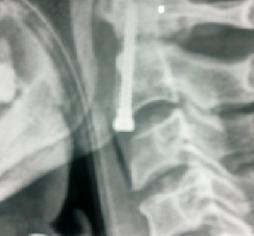

Odantoid Fracture

Cervical Vertebral Fracture